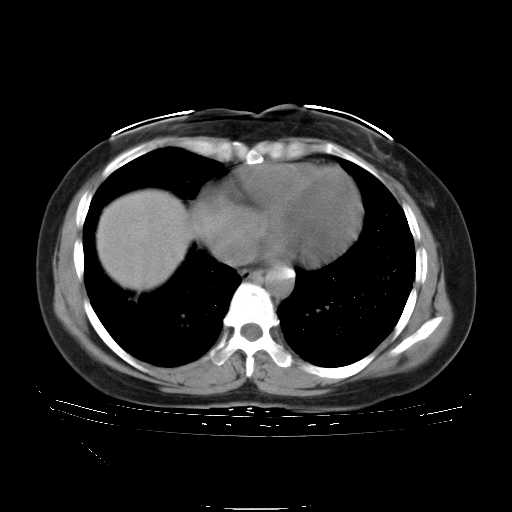

下面是今天刚刚做的,在上海治疗,吃了家属也说不清的一种药,一个月1万左右,

考虑  腺癌肺内转移,治疗较前病灶缩小、减少

肺癌并肺内转移,这种疾病治疗后在影像上看略有好转,不是很显著,但是肿瘤治疗效果影像只是一方面。

支持肺癌并肺内淋巴管炎,  原发灶小了,但转移较前片明显了.

支持右肺下叶周围型肺癌并肺内淋巴管炎,  原发灶小了,但转移较前片明显了.。